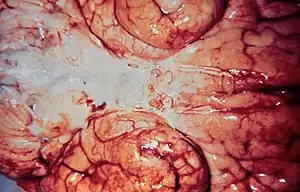

| Haemophilus influenzae meningitis | |